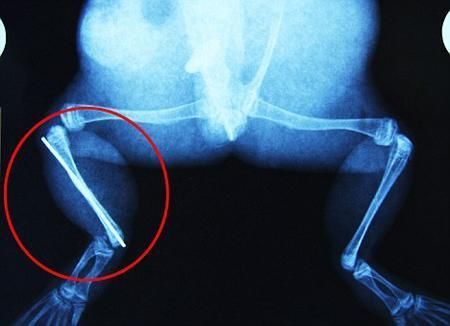

環球網4月2日報道 據《每日郵報》報道,上個月,南非大牛蛙布魯萊的右小腿被鄰居家的一只狗咬到,導致粉碎性骨折,現在經過2個小時的手術,它的斷腿已經被接上,它也因此成為有史以來第一只通過外科手術用鋼針接上斷腿的青蛙。

野生生物專家安妮經常為學校寫教材,她認為這是人類第一次通過手術給一只青蛙接斷腿。在手術開始階段,獸醫把少量給狗用的麻醉藥注入到這只青蛙體內,讓它失去知覺。然后他在布魯萊的斷腿上切開一個小口,把一根小鋼針植入腿里。最后獸醫給它縫了9針,把切口縫合在一起。僅僅幾周后,布魯萊就能在安妮家附近活動了。這只青蛙大約已有25歲,主要以嚙齒動物、蛇和其他青蛙為食。布魯萊所屬的牛蛙種群正在不斷減小,目前只能在非洲南部的濕地里才能看到這種青蛙。

安妮有2個孩子,她已經從事20多年兩棲動物保護工作。她認為鄰居家的狗狗在把布魯萊從地下刨出來的時候,它正在地下冬眠、她說:“世界上只有這個地區能看到這種牛蛙,這種青蛙現在變得越來越稀少。因為我從事野生生物保護工作,因此認識很多兩棲動物專家,但是以前他們誰也沒見過這種事情。看到布魯萊越來越健康我非常開心。現在還需要一段時間,它的金屬腿和它的骨骼才能融為一體,那時布魯萊會跟以前一樣健康。我們認為這個過程需要幾周時間,但是一旦它完全康復,我希望把它放歸大自然,讓它重新回到它最鐘愛的濕地里。”